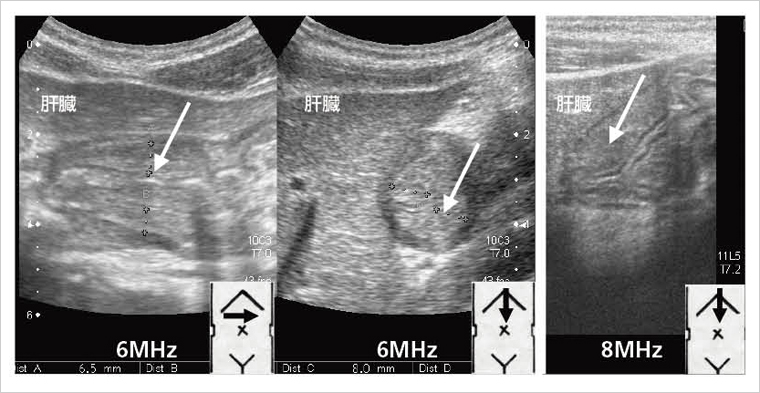

肥厚性幽門狭窄症の特徴は,生後1か月前後から始まる噴水状の嘔吐で,吐物に胆汁を含まない。放置すると状態が悪化するが,最近の症例は受診が早いので,状態が悪化していることはほとんどない。図3に,肥厚性幽門狭窄症の超音波所見(6MHz)を示す。図3 aが幽門部の縦断像,図3 bが横断像であるが,肥厚した筋層がはっきりと描出されている。通常は5〜6MHzで全体像を観察し,引き続いて7.5〜8MHzで詳しく検索するのがよい。描出のコツは肝臓をエコーウインドウにして幽門部を描出すること,右側臥位にして幽門部に胃内容を移動させ,ガスの影響を避けることである。

図3 肥厚性幽門狭窄症

急性胃粘膜病変は,何らかの精神的ストレスが誘因となり,急激な上腹部痛と嘔気・嘔吐を来す疾患で,内視鏡で胃前庭部に粘膜の発赤,びらん,浅い潰瘍を認める。年長児に多いが,最近では幼児例も経験する。本症は臨床症状とエコー所見のみで診断可能な疾患のひとつである。輸液でなかなか軽快しない心窩部痛や嘔吐を認める場合には,本症を疑ってエコーを行うことが重要である。エコーでは,胃前庭部の肥厚(主に粘膜下層)を認める(図4)。低エコーの筋層の内側に高エコーの粘膜下層が描出されているが,8MHzの高周波プローブでよりはっきりしている。急性胃粘膜病変は内視鏡的診断名であり,成人では内視鏡検査の適応かもしれないが,小児では診断のための内視鏡検査は必要ないと考えている。なぜなら,H2ブロッカーの投与で速やかに軽快し,エコー所見も約1週間で正常化するからである。

図4 急性胃粘膜病変